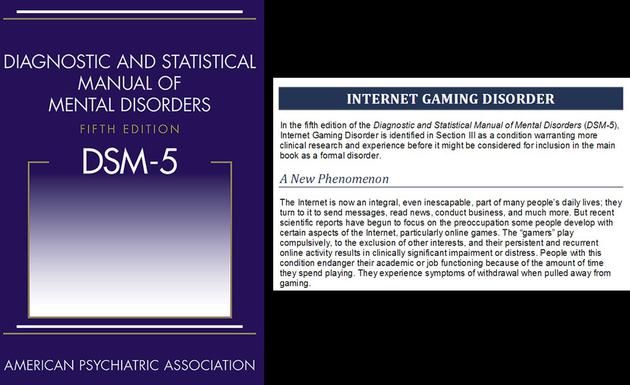

目前,学术界对网络游戏成瘾究竟是不是一种精神疾病还存在一些争议。美国精神病协会2013年正式出版的《精神疾病诊断与统计手册第五版》(DSM-5)中将 “网络游戏成瘾”列为“有待更多研究的情形”。2018年6月,世界卫生组织(WHO)在第11版《国际疾病分类》(ICD-11)中,将“游戏成瘾”正式列为精神疾病之一(ICD编码6C71)。WHO给出的“游戏成瘾”包含以下特征:1)对电子游戏自控力低下;2)将玩游戏的优先级至于其他兴趣和日常活动之上;3)在明知有负面后果时,仍会坚持玩游戏;4)以上情况持续12月以上。DSM-5和ICD-11中列入“游戏成瘾”,是基于近年来大量关于网络(游戏)成瘾基础研究的成果,也反应了全球范围内多数精神病学家和相关领域专家学者的共识。

美国精神病协会2013年正式出版的《精神疾病诊断与统计手册第五版》(DSM-5)中将 “网络游戏成瘾”(Internet Gaming Disorder)列为“有待更多研究的情形”

美国精神病协会2013年正式出版的《精神疾病诊断与统计手册第五版》(DSM-5)中将 “网络游戏成瘾”(Internet Gaming Disorder)列为“有待更多研究的情形”为何未成年玩家爱玩网络游戏